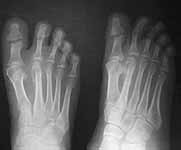

HISTORY: 25 year old engineer presented with a swelling right foot in the region of 2nd MTP joint. He noticed this swelling about three months ago following which a POP cast was applied elsewhere presumably under the diagnosis of a fracture. On removal of cast the swelling was persisting and may be was a bit more prominent. He gives h/o multiple ulcers in both the feet for which a diagnosis of trophic ulcers were made.

His younger brother was diagnosed to have "Genetic neuropathy" when he developed trophic ulcers. This brother subsequently developed a similar swelling which was finally diagnosed (after the initial diagnosis of fracture) to be a calcified chondroma and a second toe ray amputation was done few years ago. He subsequently lost first toe on the same foot following trophic ulcers. Strong family history of consanguinity in the parents. I am attaching three serial X rays of lastfour months. Is it a tumour around 2nd metatarsal or is it a healing stress fracture?? Thanks in advance.

Nov 2003

Looking at the sequential radiographs, I would say this is a healing fracture. The question is whether there is something going on that predisposed the metatarsal to fracture (i.e., tumor, infection, neuropathy,etc.). I would initiate vascular workup (arterial and venous), infection workup (CBC with differential, ESR, C-reactive protein),diabetes mellitus/neuropathy workup and follow the fracture healing. At some point an MRI may be helpful, but at this point you'll just see a large reactive zone (inflammation) due to the fracture healing and I doubt it would help narrow the diagnostic possibilities. I'm sure there is better advice out there. Good Luck!

I think its a healing fracture but the history just does not add up right.